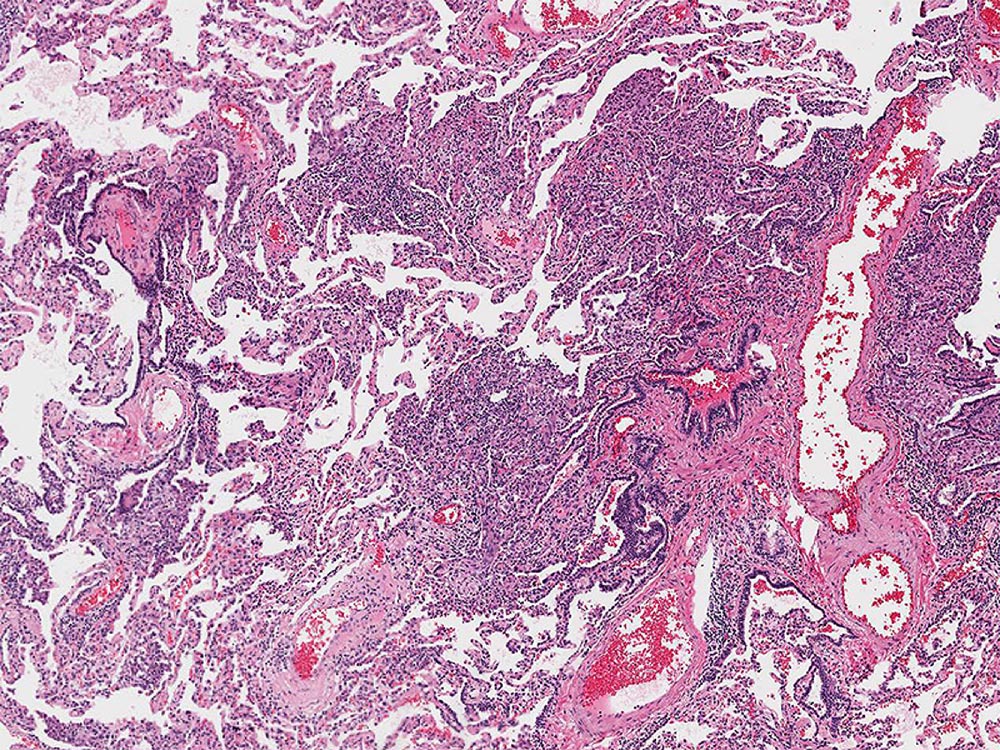

Histopathology Gallery

Histology